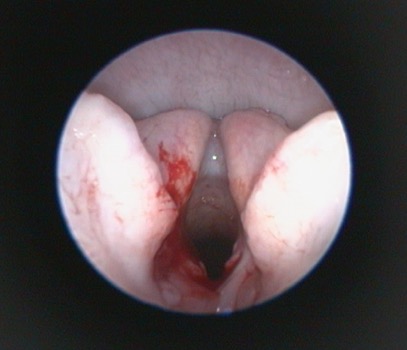

Additional diagnostic tests that can give information beyond the direct preoperative visual observation of the nostrils, soft palate (Figure 1), tonsils, laryngeal saccules (Figure 2) and laryngeal cartilages can include thoracic radiographs, computed tomography (CT) and pharyngoscopy/rhinoscopy. Findings can include aberrant nasal turbinates, aspiration pneumonia, hiatal hernia (and other oesophageal conditions), nasopharyngeal mucocoele and tracheal/bronchial disease.